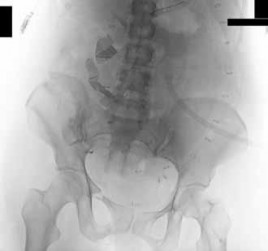

-Figures 10a and 10b are the radiographs of a 33-year-old man who was involved in a high-speed motorcycle crash. He sustained an isolated injury to the right lower extremity. On the day of injury, he was treated with open reduction and internal fixation of the femoral neck and retrograde nailing of the femur.

Radiographs are shown in Figures 10c through 10f. Alternative treatment with a cephalomedullary device alone would be more likely to lead to which of the following outcomes?